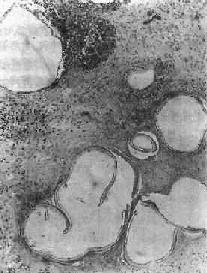

图19-20 肝泡状棘球蚴病

可见多数大小不等的小囊泡,仅见角皮层而不见生发层,囊内无头节,囊泡间组织呈凝固性坏死